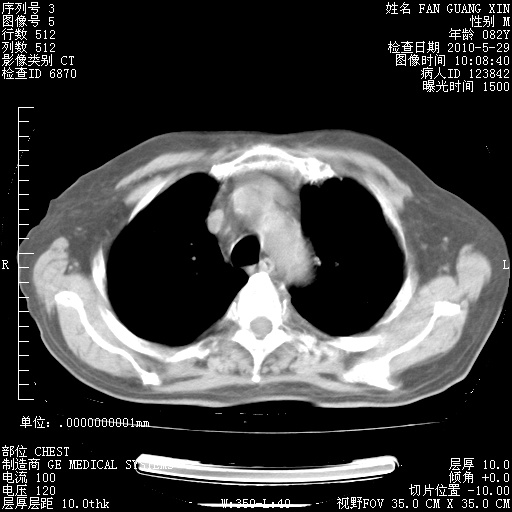

再治疗10天后的肺部CT 纵膈窗

阅读此次胸部CT,肺间质渗出性改变较入院时有吸收。目前从体温、白细胞、中性分叶明显增高,肯定存在细菌感染(发生医院感染哦,若无消化道及泌尿系统等感染的依据,肺部感染可能大)。若你院头孢哌酮舒巴坦钠耐药率较高,同意你的方案,若48小时体温仍高,可考虑使用碳青霉稀类抗菌药物,同时可予超声雾化、注意滴数时加大液体量。白蛋白33.30g/L较低哦,需加强营养等支持治疗。